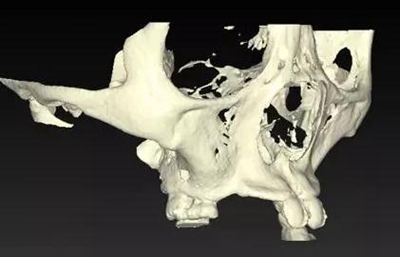

??茩z查:口內(nèi)僅剩16,11,21,26,雙側(cè)上下頜乳牙E滯留,其余恒牙缺失,上下頜骨發(fā)育不足,缺牙區(qū)牙槽嵴呈刃狀,上下頜弓比例協(xié)調(diào)。CBCT顯示:上頜前牙區(qū)牙槽嵴寬度約2-3mm,骨高度約10mm;上頜后牙區(qū)可用牙槽骨高度僅1-2mm,左右側(cè)上頜

竇內(nèi)粘膜有明顯增厚。下頜牙槽骨寬度及高度嚴(yán)重不足,僅存有基骨。